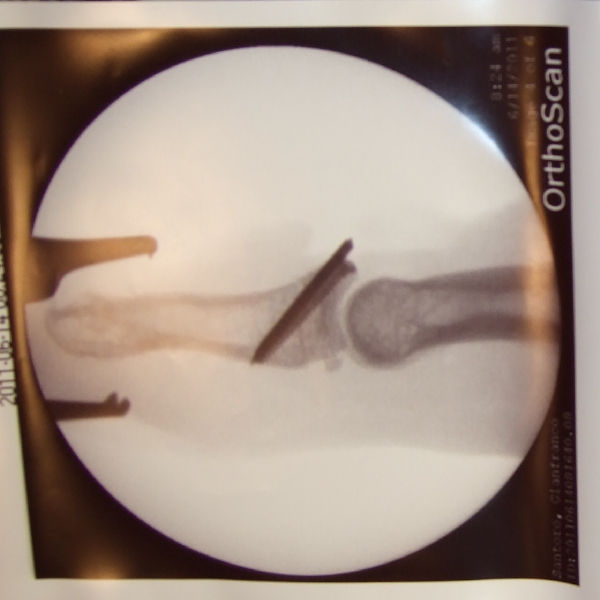

So... nach der OP (ging alles super)

Zwei Bilder für Euch. Auf dem Orthoscan ist zu sehen wie das Gelenk abgebrochen war/ist.